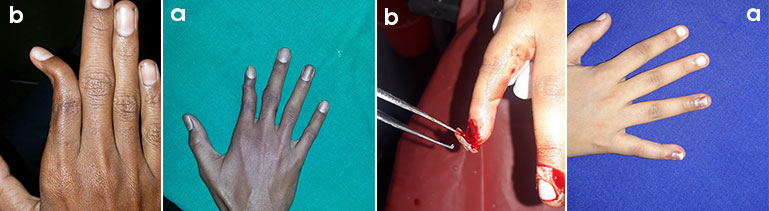

Finger & Toes deformities After Before Images

Microsurgery is a surgery done under magnification for reattaching fingers, toes, hands, foot and also in correction of traumatic and congenital deformities.